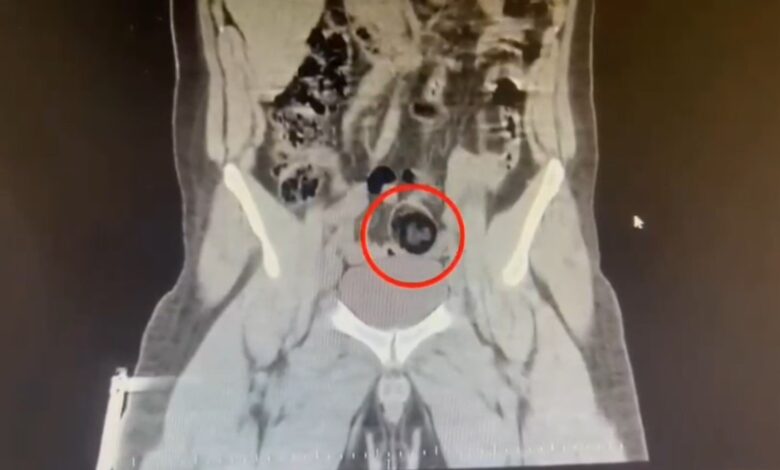

Şüpheli hareketler sergilen kurye götürüldüğü hastanede yapılan iç vücut muayenesinde makatında cisim olduğu anlaşıldı.

MAKATINDAN 105 GRAM UYUŞTURUCU ÇIKTI

Kuryenin makatındaki 105,98 gram metamfetamin gerçekleştirilen cerrahi müdahaleyle çıkarıldı.